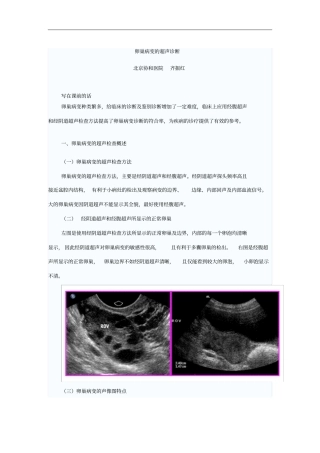

卵巢病变的超声诊断北京协和医院齐振红写在课前的话卵巢病变种类繁多,给临床的诊断及鉴别诊断增加了一定难度,临床上应用经腹超声和经阴道...